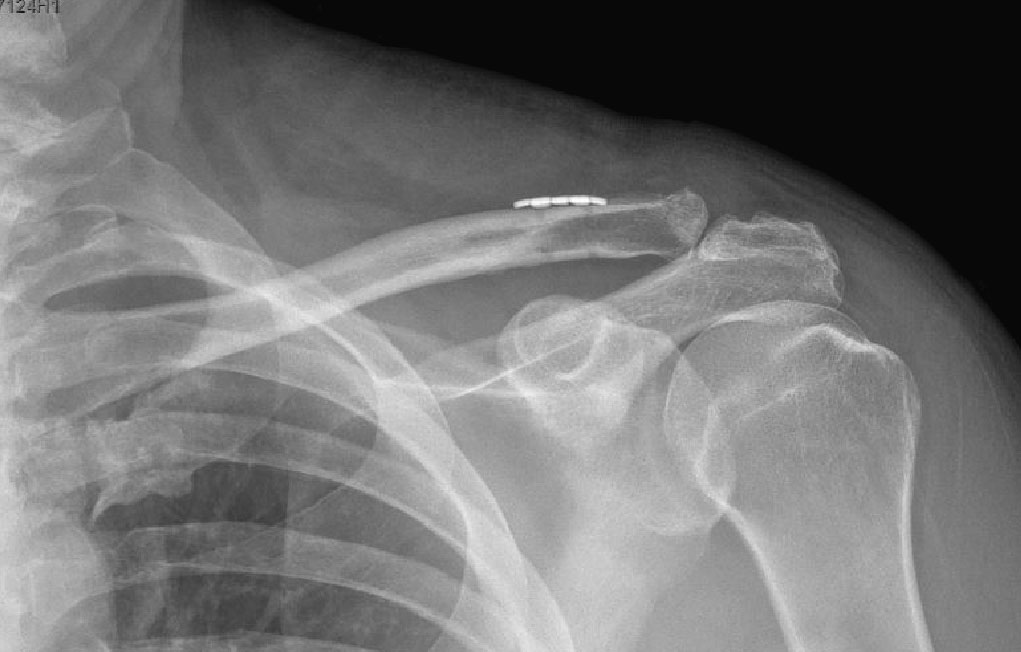

I operated on Tony later the same day and, after an overnight stay in a Sydney hospital, he was able to travel 4 hours home. Tony reported feeling significantly better after the surgical stabilisation of the joint. Below is the x-ray just one week after surgery.

AC joint dislocation after surgery